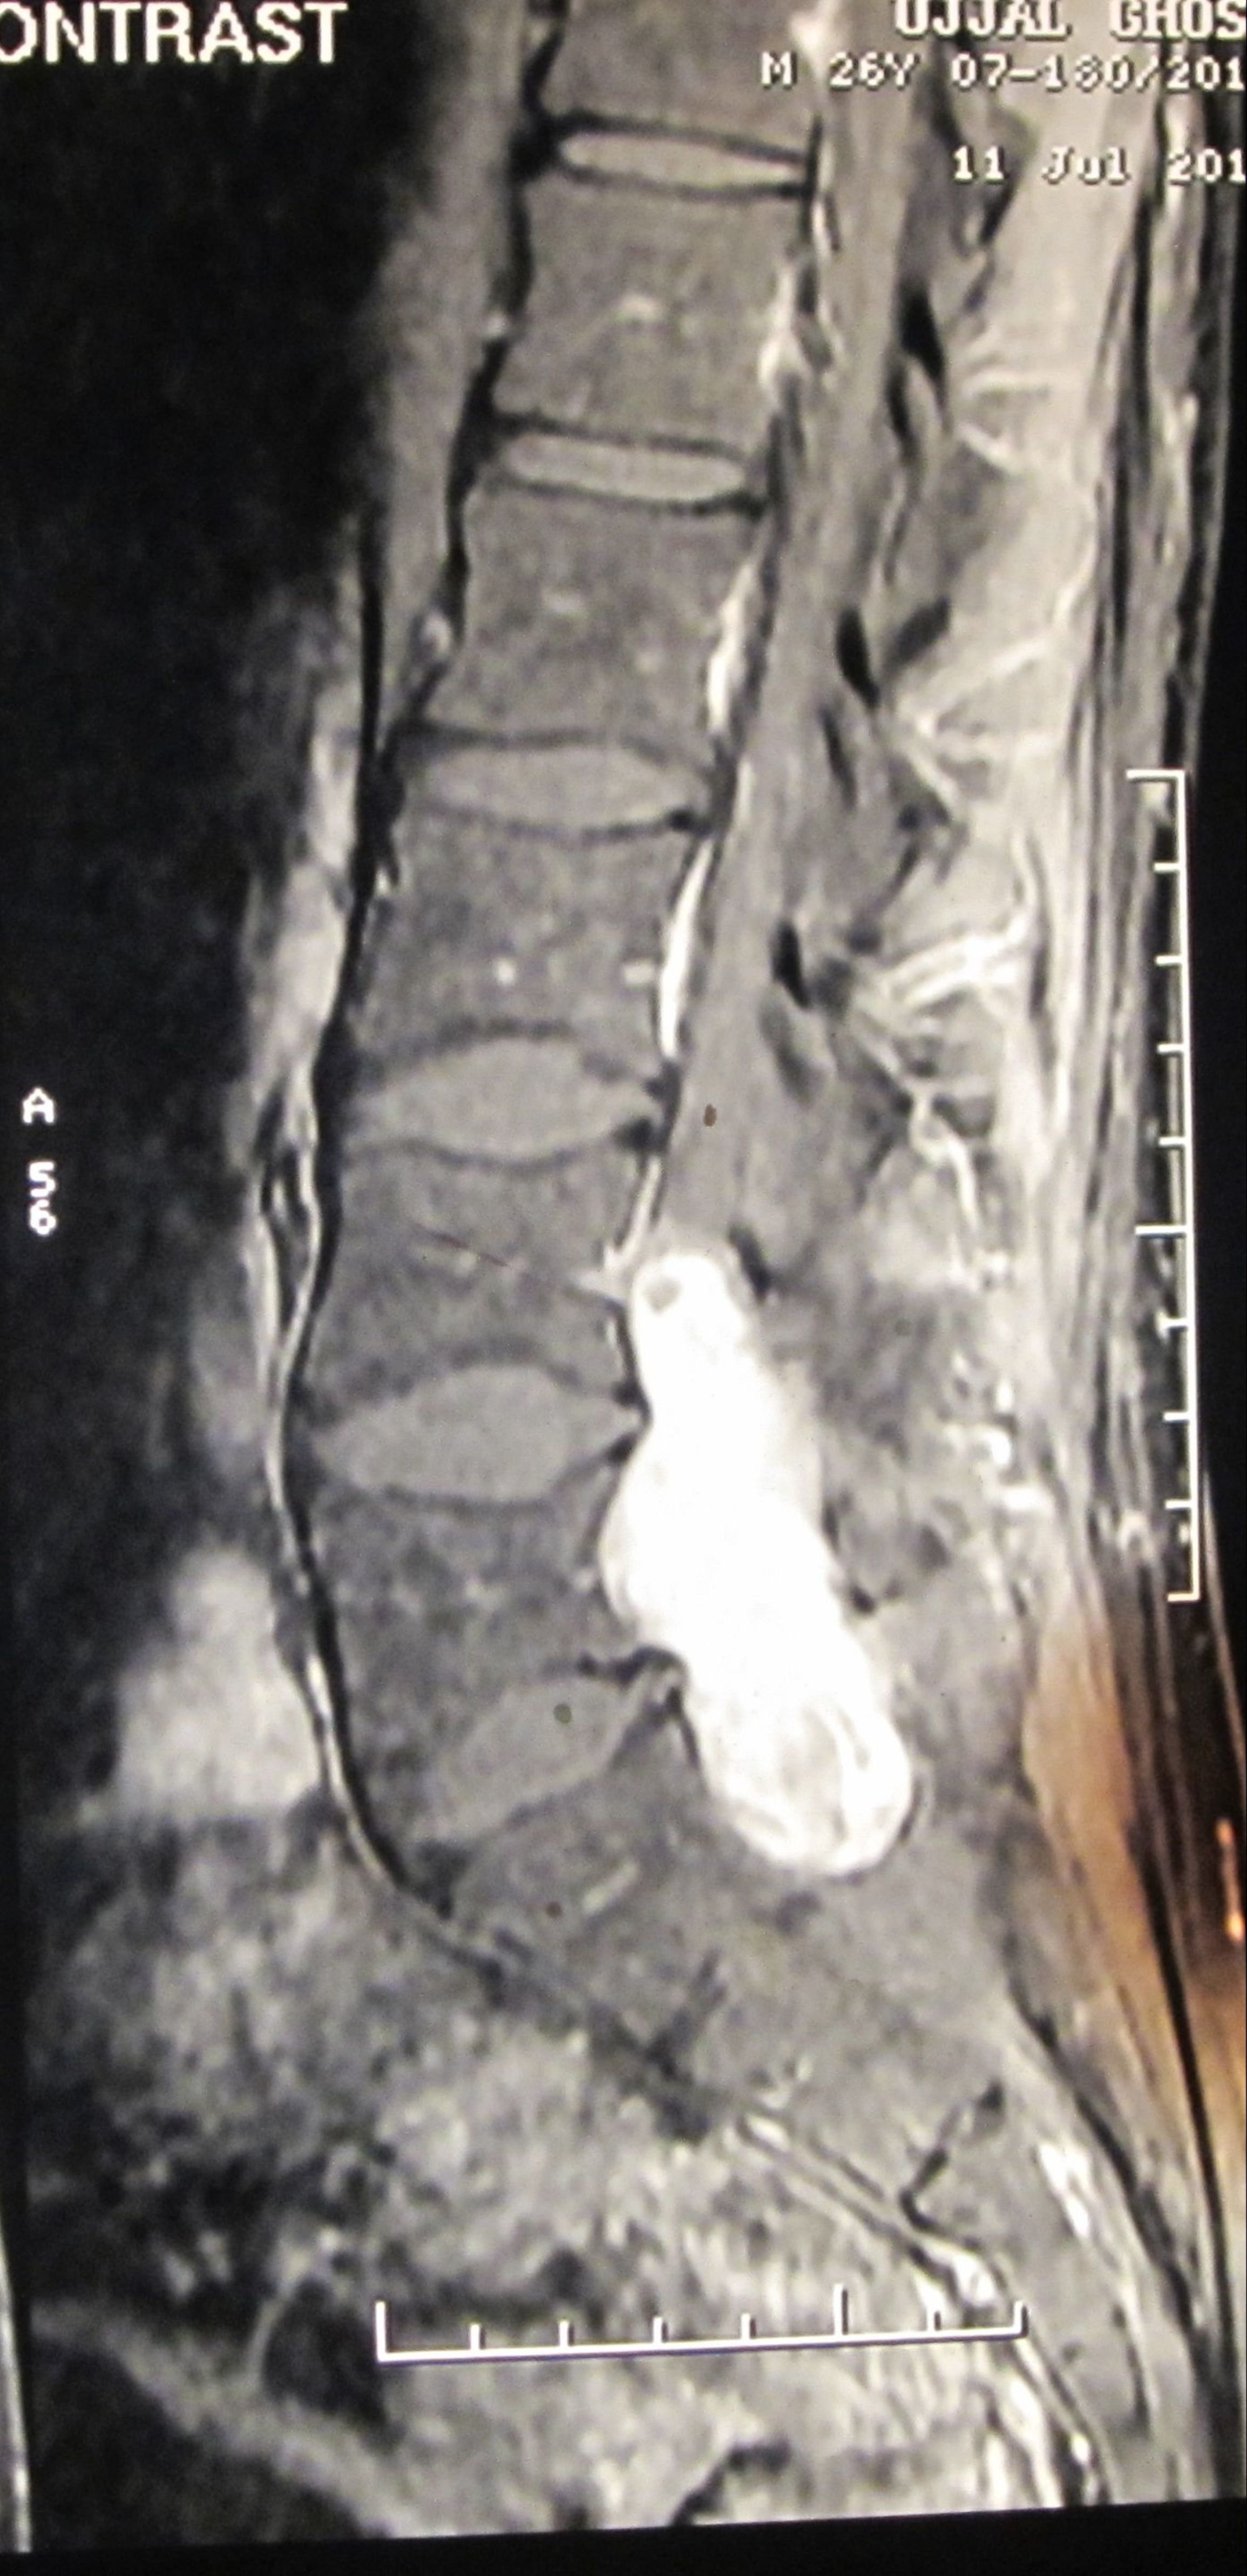

Filum terminale paraganglioma is a rare tumour with usual short segment spinal involvement (one or two segments) as described in various literatures. It can also present with long segment spinal involvement as in our case, the tumour has involved L4 to S1 segments. Prognosis of filum terminale paraganglioma is excellent after total excision as it is classified under WHO grade I tumor. Nonetheless, after subtotal removal, tumour recurrence can occur. Even such an extremely rare entity with a larger spectrum of presentation can be treated successfully by total removal of the tumour. Here we present a fi lum terminale paraganglioma which was diagnosed after histopathology and immuno-histochemistry. Patient made a full recovery after tumour removal.